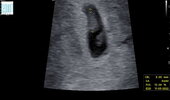

Kurcze oglądam Wasze zdjęcia i wszystkie macie ten pęcherzyk taki okrąglutki a u mnie zarodek 5mm w takim podłużnym kokonie 🙈 wtedy było 6+2

U mnie tez raczej podluzny. Czy to zle? 🙈

Załączniki

• E3E551A8-F121-43E8-9A7C-75B00CDBD9F3.jpeg

E3E551A8-F121-43E8-9A7C-75B00CDBD9F3.jpeg

71,7 KB · Wyświetleń: 71